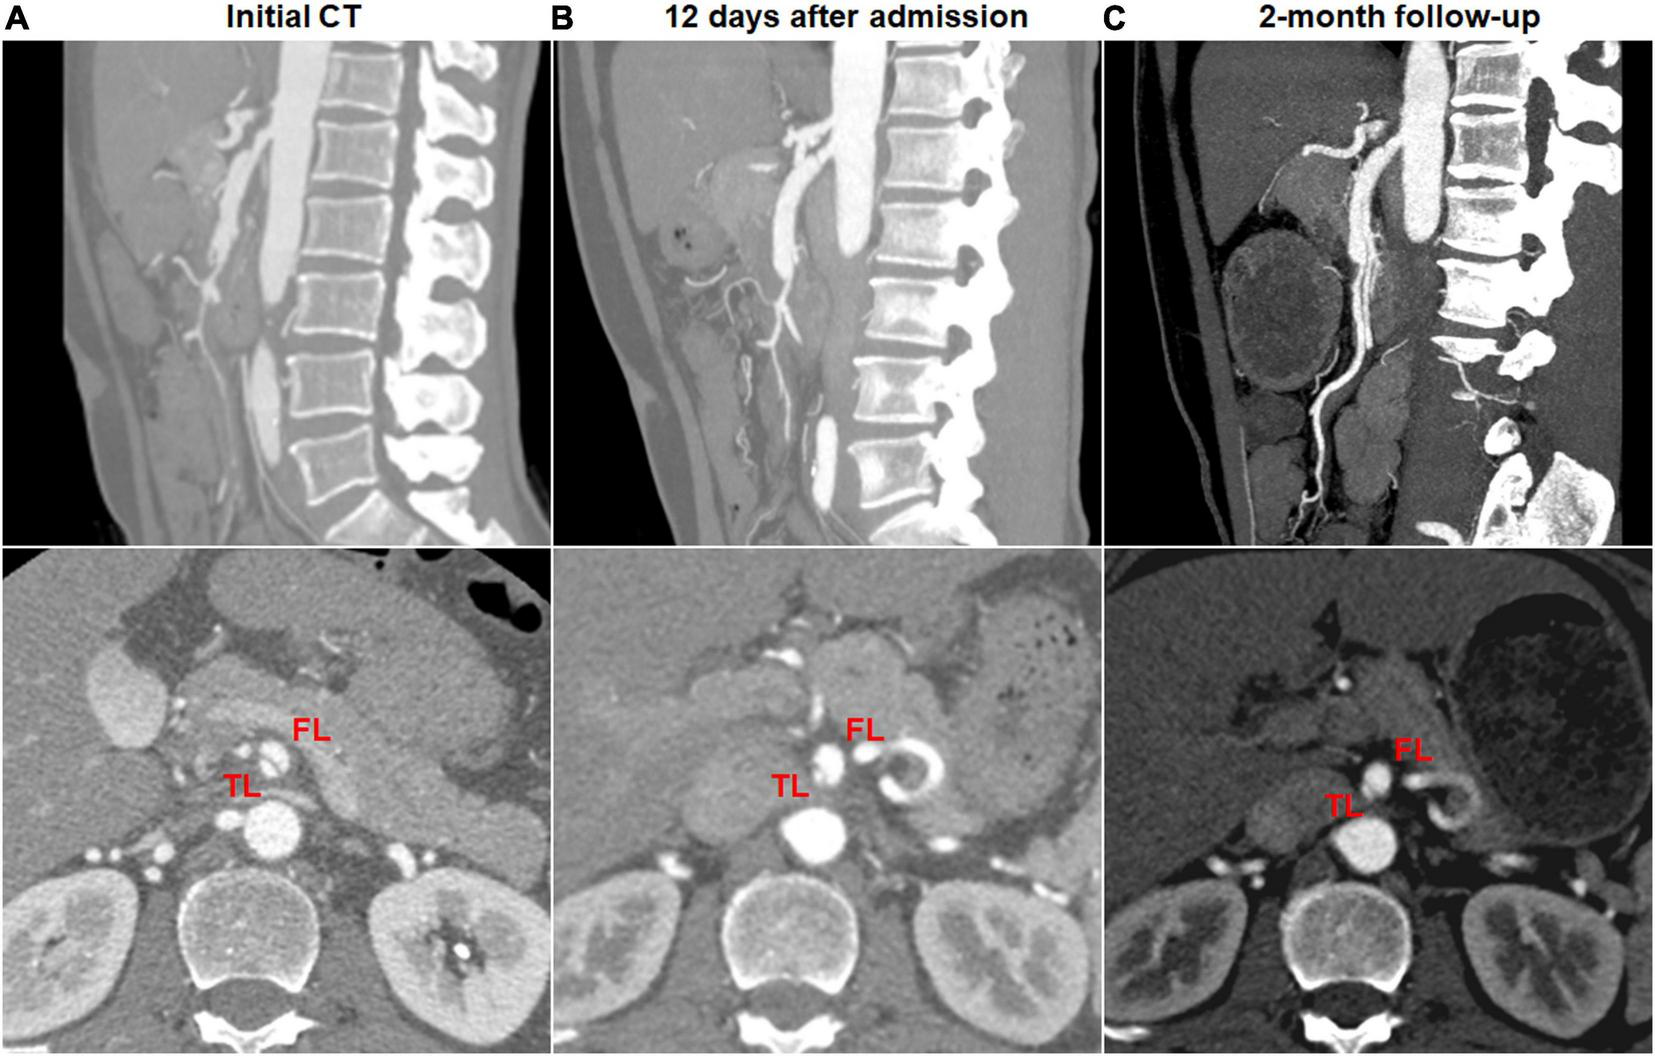

Dissection progression on CTA occurred in 9 (27.3%) of 33 type II dissections of “cul-de-sac” shaped FL without re-entry (Figure 8). The mean diameter of TL declined from 2.8 ± 0.7 mm on initial CT to 1.3 (1.1; 1.7) mm on follow-up CT (p = 0.003). The mean diameter of FL increased from 5.3 ± 0.7 mm on initial CT to 7.2 ± 1.0 mm on follow-up CT (p < 0.001).

FIGURE 8

Morphologic progression of type II spontaneous isolated superior mesenteric artery dissection on follow-up computed tomography (CT) angiography. (A) Initial CT angiography showed the patent “cul-de-sac” shaped false lumen without re-entry in a 48-year-old man. (B) Twelve days later, blind-ending false lumen was prolonged and compressed the true lumen despite symptomatic relief. (C) Two months later, the false lumen was further enlarged, and true lumen remained severely stenosed.